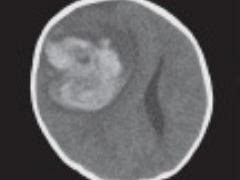

Trauma-incident bij een patiënt met stollingsstoornis Lees meer over Trauma-incident bij een patiënt met stollingsstoornis Trauma-incident bij een patiënt met stollingsstoornis

Patiënten met een stollingsstoornis worden niet altijd herkend op de Spoedeisende Hulp, toch is dit van levensbelang. Er zijn verschillende stoornissen, waaronder hemofilie en de ziekte Von Willebrand. Bij hemofilie ontbreekt volledig of gedeeltelijk het stollingseiwit factor 8 (VIII, hemofilie A) of factor 9 (IX, hemofilie B). Afhankelijk van de ernst, kunnen bloedingen optreden in gewrichten, spieren of bloedingen na een medische ingreep of trauma. De ziekte Von Willebrand komt voornamelijk tot uiting via slijmvliesbloedingen of als (na)bloedingen na een medische ingreep, met name na een kiesextractie of tonsillectomie. Deze aandoeningen vragen een specifieke behandeling bij een trauma. Het is van belang dat bij een trauma binnen drie uur stolling wordt toegediend, om inwendige bloedingen te voorkomen, voordat verdere diagnostiek plaatsvindt.